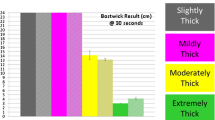

The number of diagnostic test materials for videofluoroscopy (modified barium or iodine swallow) available on the market is large and the proposed consistencies can be very different. Figure 2 shows the variation of the shear viscosity as a function of shear rate for seven liquid contrast materials, all measured at a temperature of 20 °C (where the viscosity of pure water is 1 mPa s), first at increasing shear rates (from 0.01 to 100 s−1) and then decreasing ones (from 100 to 0.01 s−1). The shear rate of 50 s−1 (specified by the NDD guidelines) is highlighted, as this is where materials should be compared according to the NDD standard.

Data for two commercial thickeners (starch-based TU and xanthan gum-based TUC) used to modify beverage and food consistencies for people suffering from dysphagia are shown in Fig. 3. For TUC, data are shown at several different concentrations corresponding to the different levels: nectar-like, honey-like, and pudding-like (see Table 2).

Viscosities of thickened solutions at different consistencies (nectar, honey, pudding) obtained using two commercial thickeners: Resource® ThickenUp™ Clear (TUC) and Resource® ThickenUp™ (TU). Solution concentrations were chosen following recommended dosages of the thickener products (see Table 2)

The viscosity variation with shear rate, over a wide range of shear rates thought to be relevant as experienced by the bolus during the swallowing process, was studied for a large number of videofluoroscopic contrast fluids available on the market (Fig. 2). It is readily seen that comparing viscosities not obtained at the same shear rate can lead to highly misleading conclusions, e.g., even the Varibar® pudding consistency has a lower shear viscosity measured at a high shear rate than the Varibar® nectar consistency measured at a low shear rate! In general, a strong decrease in viscosity with increasing shear rate (i.e., shear-thinning) is observed for all the materials except for Varibar® Thin Liquid and Gastrografin® (pure or diluted with water).

When comparing viscosity values at 50 s−1, all grades of the Varibar® range are clearly distinct and the order corresponds to the different stated levels; however, some of the denominations (e.g., Varibar® honey) do not correspond to the range defined by the NDD standard (Table 3). This observation is also valid when viscosity values at 30 s−1 are considered (as specified by the manufacturer). Due to different shear-thinning behaviors, fluids like Varibar® pudding and Varibar® honey have significantly different viscosities at low shear rates, but at shear rates above 50 s−1, the differences are within 25 % variation and lower. Moreover, E-Z-Paque® has a viscosity essentially identical to the Varibar® nectar and thus is substantially more viscous than water. It should therefore not be considered a “thin liquid” in swallowing studies, as its viscosity is at least 100 times higher than water for shear rates up to 100 s−1. The fact that all materials measured showed—within the precision of measurement—no differences between shear viscosity at increasing and decreasing shear rate means that they do not exhibit shear history dependence: the shear viscosity is influenced by the shear rate (speed of flow), but not by how this shear rate is reached, an important point for consistent performance of these fluids during examination. For example, if a test sample is administered to a patient using a syringe (to control its volume), this sample is subjected to very high shear rates in the tip of the syringe. If the sample has a shear history dependence, then its behavior during swallowing and the viscosity perceived by the patient might be different from the case where the sample was administered from a spoon. Minimizing effects of shear history dependence is thus very important.

When the viscosities of liquid contrast materials (Fig. 2) and commercial thickeners at different consistencies (Fig. 3) were compared at a shear rate of 50 s−1, a close correspondence between Varibar® nectar, E-Z-Paque®, TU, and TUC at the nectar-like level was observed. For the other two consistency levels, no direct match was found and even significant differences were registered (e.g., Varibar® honey is around four times more viscous than TUC at the honey-like level at a shear rate of 50 s−1). Therefore, the link between diagnosis based on videofluoroscopic examination and prescription of thickened products that are safe to swallow is not always straightforward. One possibility to overcome this constraint could be to use the least viscous contrast material and during videofluoroscopic examination thicken it to desired consistencies using commercial thickeners, which is discussed in the following subsection.